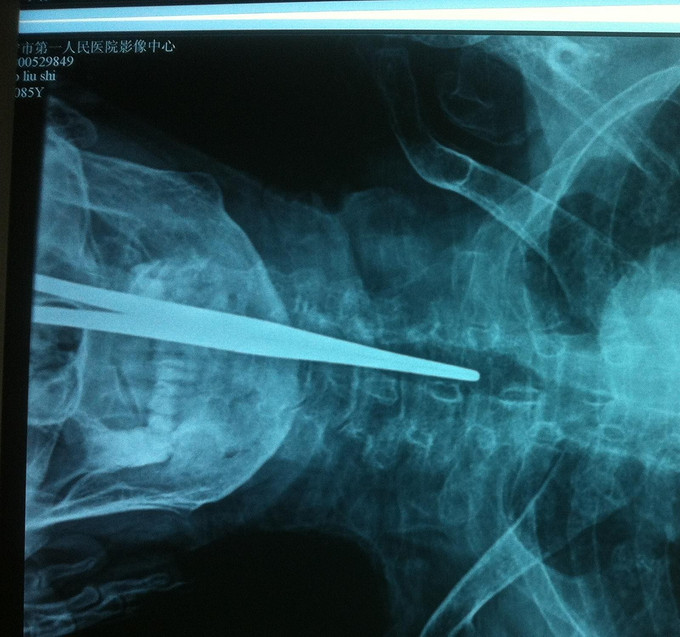

诊断:胸椎骨折 骨质疏松症 处理: 1、完善相关辅助检查,明确诊断,有无手术指证; 2、完善手术评估,有无手术禁忌,手术风险及并发症; 3、在局麻下行胸椎骨折椎体pkp术 4、术后给予全身抗骨质疏松治疗

随访 1、应常规术后1个月、3个月、半年随访; 2、术后患者背部疼痛明显减轻,术后第3日下地活动,背部轻度疼痛。 3、术后1个月,患者背部无明显疼痛,腰背部活动良好。 讨论:1、老年骨质疏松骨折的手术指征,是否能应用AO或TLIS评分? 2、老年骨质疏松骨质PKP或PVP的长期预后是否与优于保守治疗?